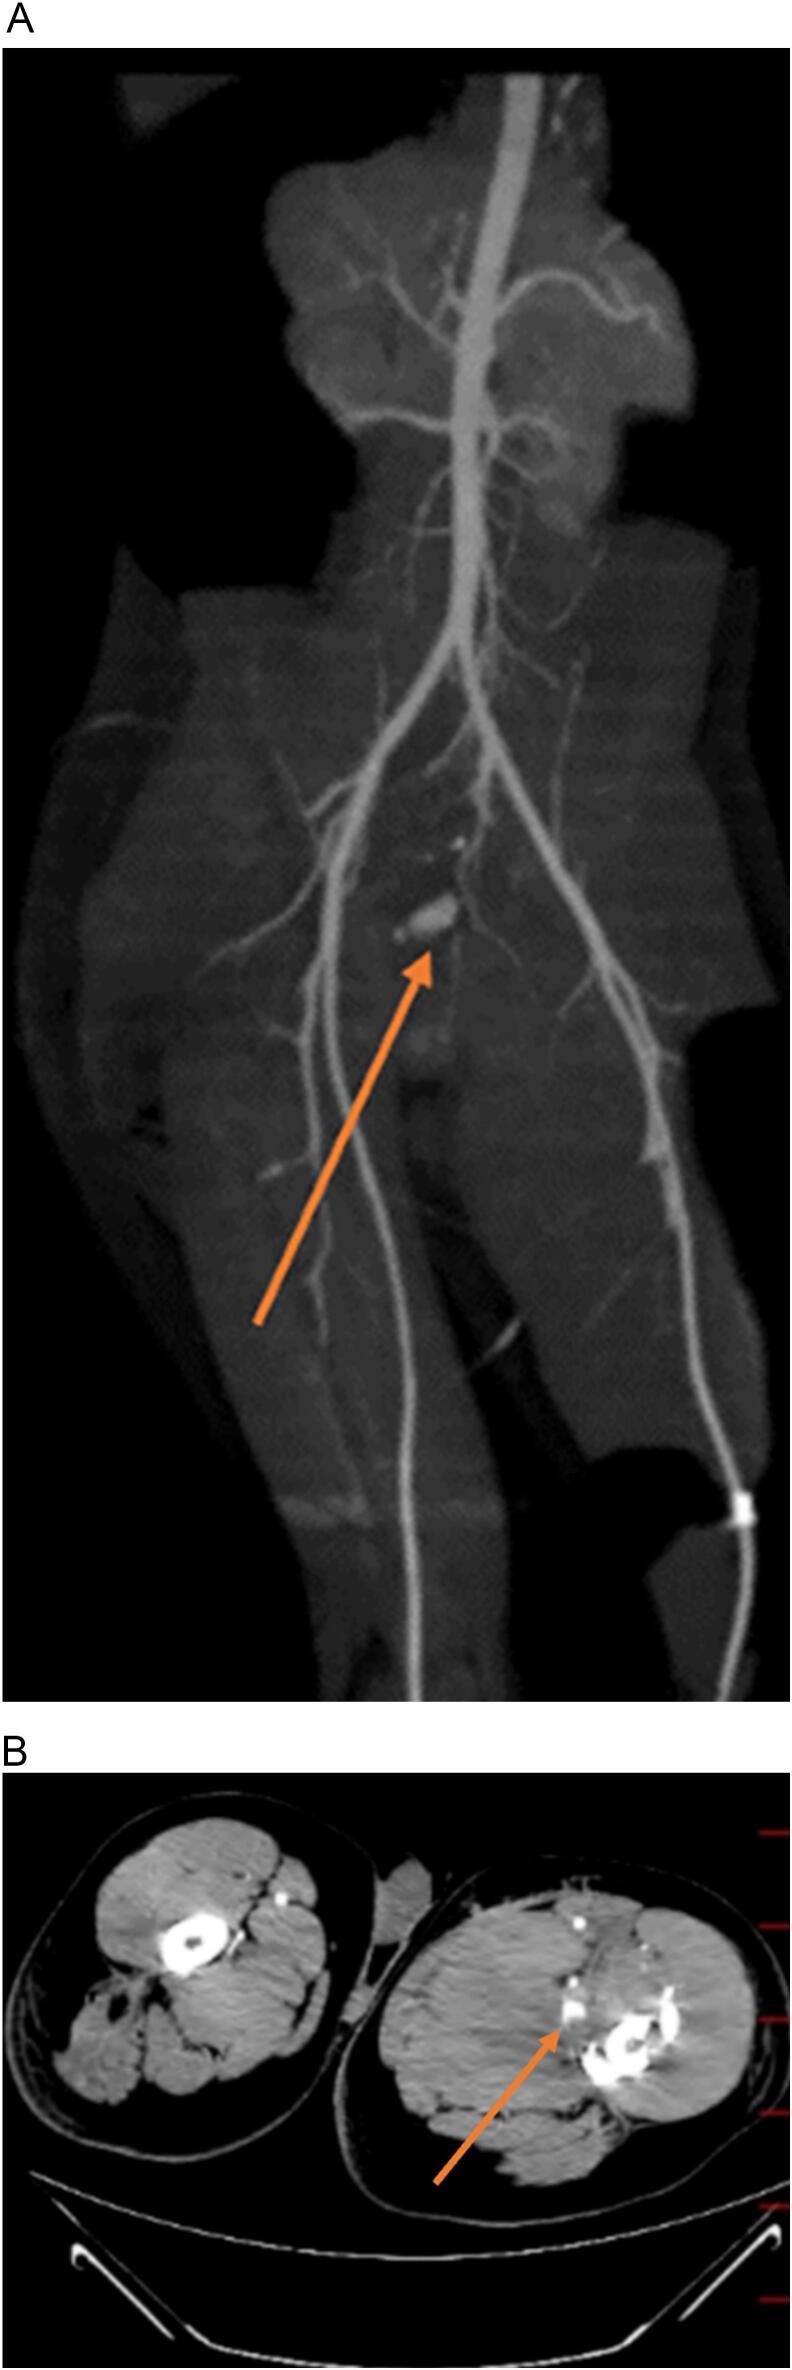

A 27-year-old male presented to the emergency department with a gunshot to the right buttock. Initial assessments revealed a left femoral shaft fracture, the right buttock as the bullet inlet and the medial portion of the left thigh as an outlet, with no other significant findings. He underwent external fixation for the left femoral fracture. On the seventh day of admission, the patient experienced two episodes of massive melena and hypovolemic shock. The patient underwent an upper endoscopy without any remarkable findings. Also, we performed an emergent laparotomy to find the source of upper gastrointestinal bleeding (GIB); however, no evidence of upper GIB was found. Then, the patient underwent CT angiography, which subsequently identified a deep femoral artery pseudoaneurysm. Also, we performed a colonoscopy to investigate the source of GIB, revealing an orifice on the rectal wall. The patient underwent open surgery for a pseudoaneurysm. During surgery, a tract from the pseudoaneurysm of the deep femoral artery to the rectum was discovered, leading to the ligation of the deep femoral artery branch. After recovery from the operation and completion of the orthopedic treatment, the patient was discharged in an appropriate condition.

一名27岁男性因右臀部枪伤被送往急诊科。初步评估显示左股骨干骨折,右臀部为子弹入口,左大腿内侧为出口,无其他显著发现。他接受了左股骨骨折的外固定治疗。入院第7天,患者出现两次大量黑便和低血容量性休克。患者接受了上消化道内镜检查,未发现任何异常。此外,我们进行了急诊剖腹探查以寻找上消化道出血(GIB)的来源;然而,未发现上消化道出血的证据。然后,患者接受了CT血管造影,随后发现了股深动脉假性动脉瘤。我们还进行了结肠镜检查以调查GIB的来源,发现直肠壁上有一个开口。患者接受了假性动脉瘤的开放手术。手术中,发现了一条从股深动脉假性动脉瘤通向直肠的通道,导致股深动脉分支结扎。术后康复并完成骨科治疗后,患者病情好转出院。